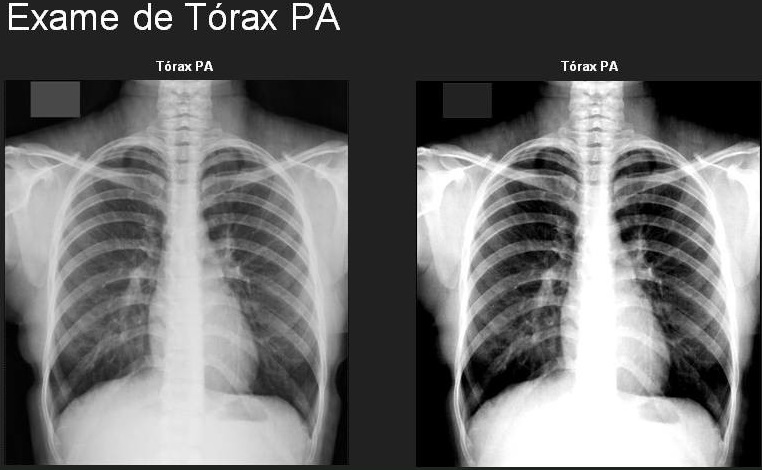

O exame de Raio X Tórax PA (Projeção Posteroanterior de Tórax) é um dos procedimentos radiológicos mais importantes e amplamente utilizados para avaliar a saúde pulmonar e cardíaca dos colaboradores. Este exame fornece imagens detalhadas do tórax, permitindo a detecção precoce de uma série de condições, como infecções pulmonares, doenças cardíacas, e anormalidades na estrutura torácica, garantindo que possíveis problemas de saúde sejam identificados e tratados rapidamente.

Para as empresas, realizar o RX Tórax PA como parte dos exames ocupacionais é uma medida preventiva essencial, especialmente em setores onde os trabalhadores estão expostos a agentes químicos, poeiras, ou onde a saúde respiratória é uma prioridade. Este exame ajuda a assegurar que os colaboradores estejam em boas condições de saúde, contribuindo para a manutenção de um ambiente de trabalho seguro e produtivo.

Oferecemos um serviço de RX Tórax PA realizado por radiologistas experientes e em clínicas equipadas com tecnologia de ponta, garantindo imagens de alta qualidade e laudos precisos. Nosso exame é conduzido com o máximo de cuidado e eficiência, assegurando que sua empresa tenha as informações necessárias para proteger a saúde dos seus colaboradores.